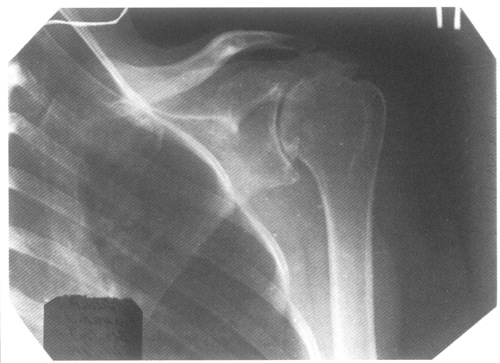

Для подтверждения диагноза необходимо рентгенологическое исследование. Лечение острых форм заболевания обычно не вызывает серьезных трудностей. Однако анкилозирующий периартрит требует длительной терапии, которую следует начинать при первых признаках воспалительного процесса. Если периартрит вторичный, терапия должна быть направлена на устранение основного заболевания. В этом случае применяются препараты, восстанавливающие кровообращение, предотвращающие разрушение хрящей и нормализующие функции печени и почек.